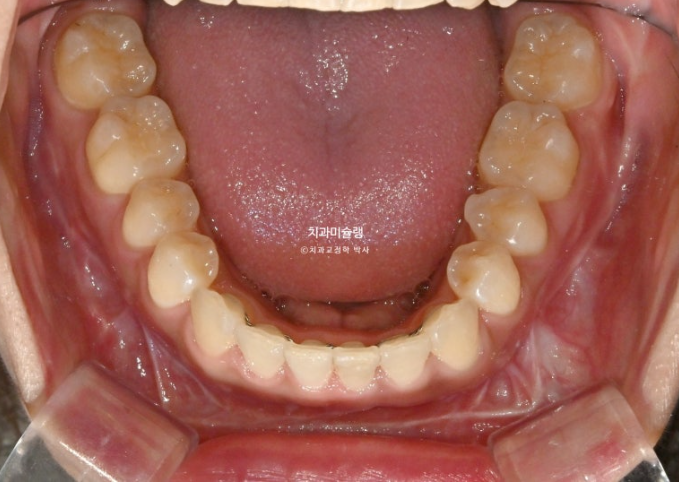

25.10

중심선은 정확히 맞으며

어금니 교합은 물샐틈 없는 1급 교합관계를 보입니다.

치근흡수는 없으며 치근평행도는 양호합니다.